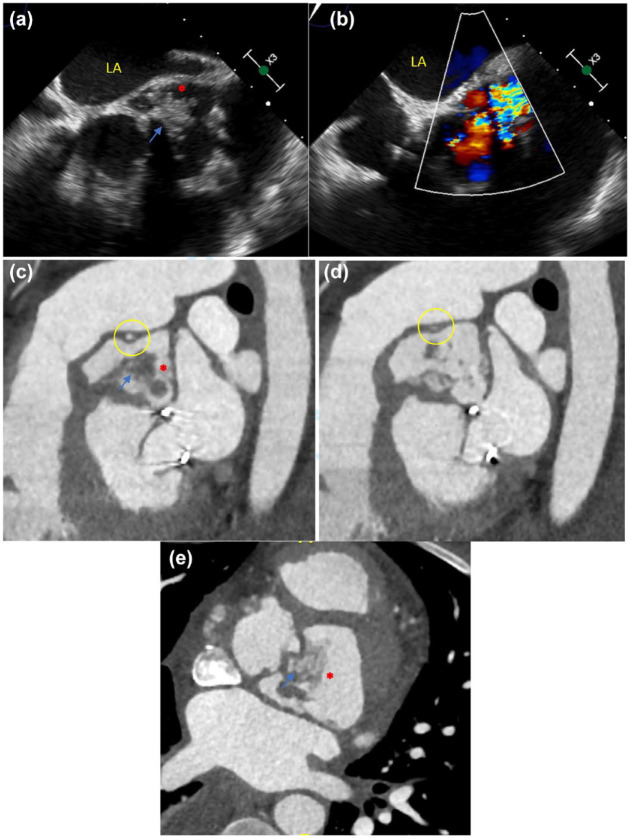

Infective endocarditis (IE) is an increasingly recognized condition with high morbidity. Patients with atypical symptoms, culture-negative infections, and prosthetic cardiac devices and implants represent challenging populations to evaluate and manage. Recent major society guidelines have recommended the appropriate incorporation of multimodality imaging in the evaluation of these more complex IE cases. This article draws on the available literature regarding the different cardiac imaging modalities and discusses the role of multimodality imaging in IE.